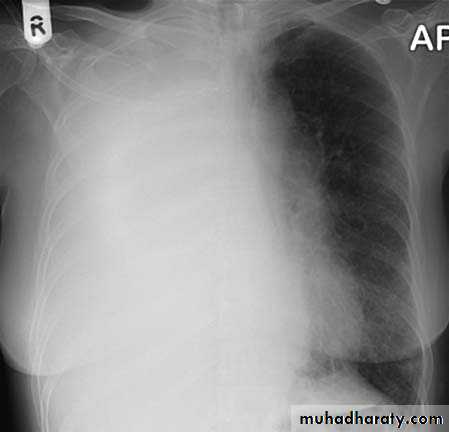

Radiopaque hemi-thoraxPneumothorax (air in pleural space )

Signs

Loss of vascular markings at the outer parts of lung fieldsDemarcating pleural line between the lung & vessels lacking area.

Well demarcating of the scapula

Epsilateral lung collapse

Tension pneumothorax

Emergency condition

Pressure effect on the mediastinum & major vessels

Treatment by chest tubes